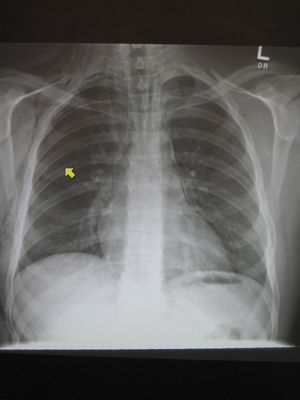

- CT Chest (preferred diagnostic test)

- CXR

- AP/PA - Ring around right pulmonary artery, air along left heart border, air in upper chest/neck soft tissue

- Lateral - air along anterior heart border

- Lateral neck - may see mediastinal air in neck

- 30% with spontaneous pneumomediastinum will have normal CXR[1]